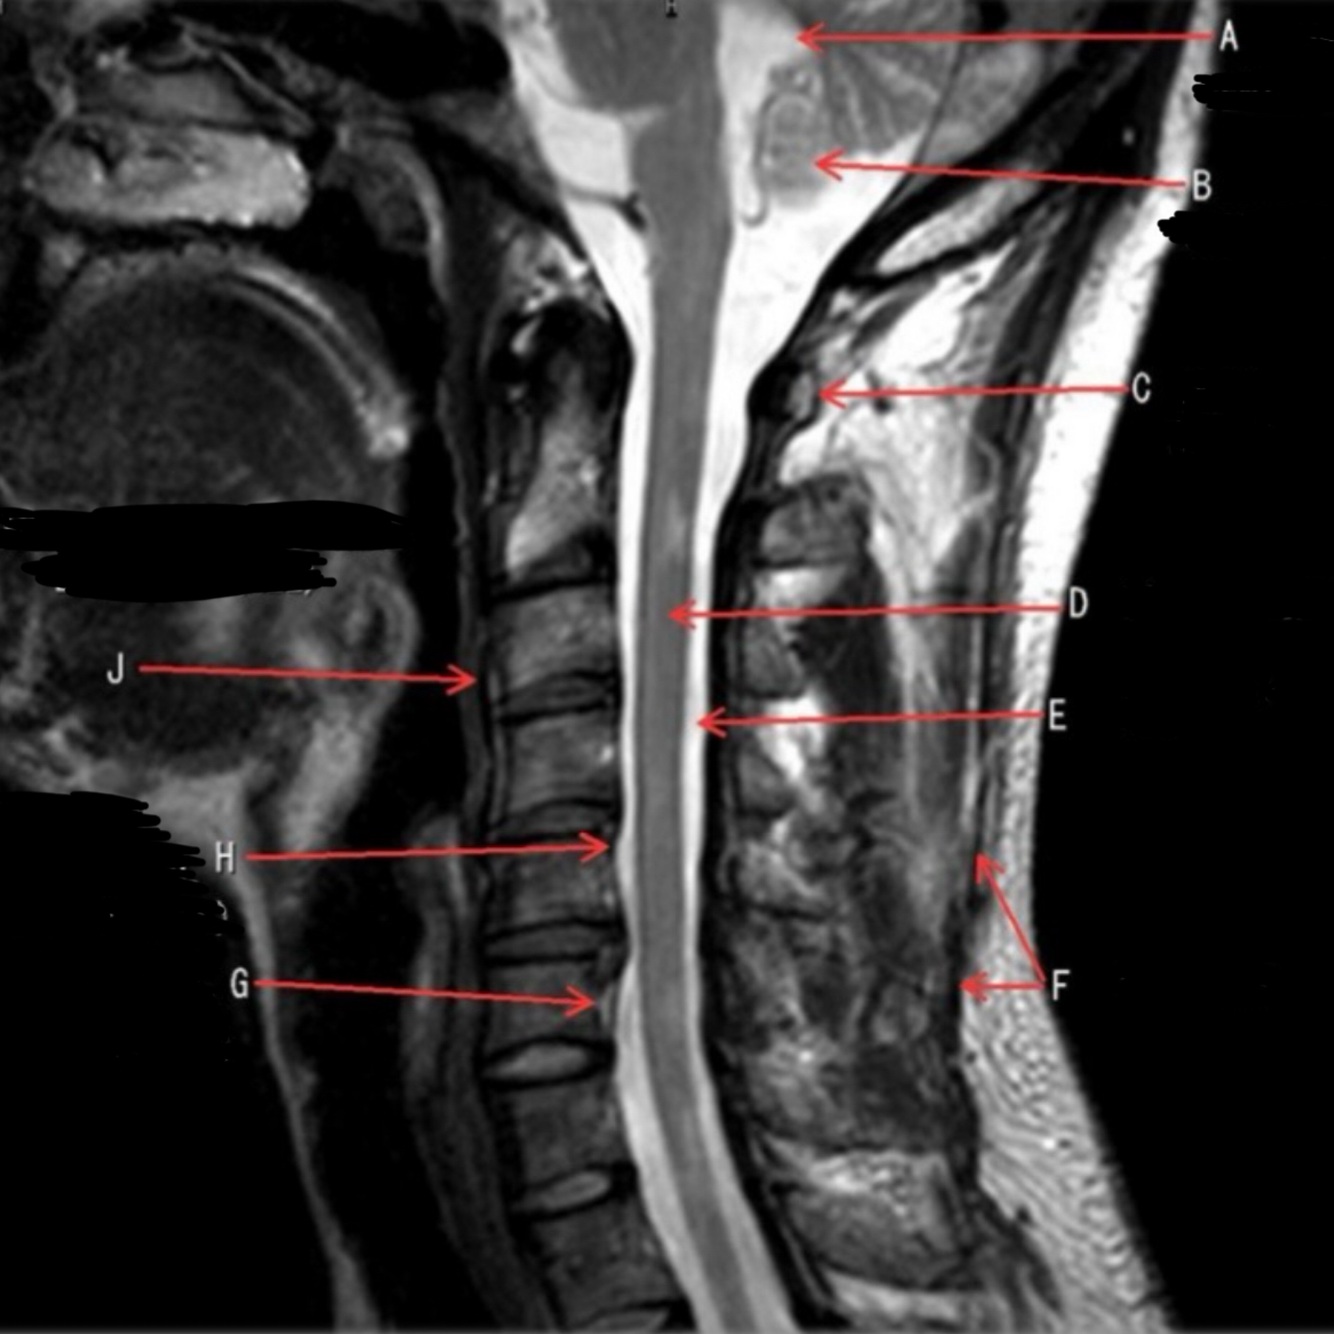

1

Q

What is letter A?

A

4TH VENTRICLE

2

What is letter B?

CEREBELLUM

3

What is letter C?

POSTERIOR ARCH OF C1

4

What is letter D?

SPINAL CORD

5

6

What is letter F?

SPINOUS LIGAMENT

7

What is letter G?

VENUS PLEXUS

8

What is letter H?

POSTERIOR LONGITUDINAL LIGAMENT (PLL)

9

What is letter J?

ANTERIOR LONGITUDINAL LIGAMENT (ALL)